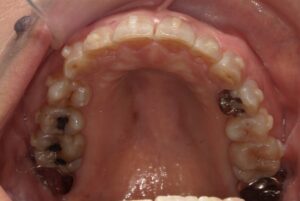

歯ぐきを切除すると共に歯を支える歯槽骨を削って、歯茎を大きく下げるイメージです。歯を長く見せる術式になります。歯肉と骨の両方を削合するので、効果を得やすいですが比較的大きな侵襲がかかります。歯が長く、歯を支える骨が十分にある歯が適応です。ただし今まで口腔内に出ていなかった歯根が口腔内に露出することになるので、知覚過敏のリスクがあります。歯そのものの長さが短いと、歯を支える骨が少なくなり歯が揺れてしまうので、適応症ではありません。

歯冠長延長術とは少し違い、メスで余分な歯ぐきだけを切除し、歯を長く見せます。ですから比較的低侵襲で行えます。歯を支える骨に問題なく、歯肉だけが多い場合が適応です。こちらも、今まで口腔内に出ていなかった歯根が露出するので知覚過敏のリスクがありますが、歯冠長延長術よりも低リスクです。切除量はさほど大きくできないので、効果は限定的です。

簡単に言うと、矯正力を使って前歯を骨の中にめり込ませる治療です。矯正用のインプラントと矯正用のゴムを用いて歯を押し下げます。期間は1〜2年程度が一般的です。この押し下げに用いる矯正力のコントロールが難しいです。また、ご自身でゴムを使ってもらわないといけないです。骨にめり込ませるというのは、指で歯を押し込むように力を加えていただくとわかると思いますが、骨の硬さにもよりますが難しいです。せいぜい1~2㎜くらいだと思ってもらうとよいかと思います。